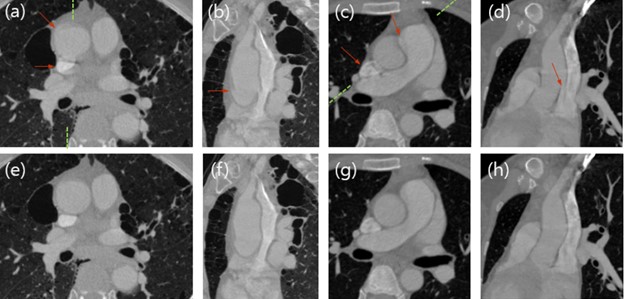

The Samsung Neurologica scientific team participated in the development of a new motion correction algorithm for X-ray lung CT imaging. The conventional CT imaging approach, which relies on segmentation to gauge motion estimation, makes the motion estimation of various fine lung structures very challenging. The novel algorithm uses two partial angle reconstruction images for motion estimation, via non-rigid registration, followed by motion compensated reconstruction. The scientific team aimed to show that their proposed method provided positive results in correcting the lung motion artifacts which arise under routine CT scans, even under breath-hold. It is important to note that these artifacts mimic various lung diseases and are a serious impediment to obtaining clear imaging and establishing best treatment for the patients.

The study shows that by using the novel algorithm which processes two reference images instead of a pure image-based approach, to provide motion information; the Technologists were able to produce significantly reduced motion artifacts of various lung structures. In addition, this method shows great potential for CT imaging of the aorta, which presents similar challenges in terms of motion estimation, as lung structures.